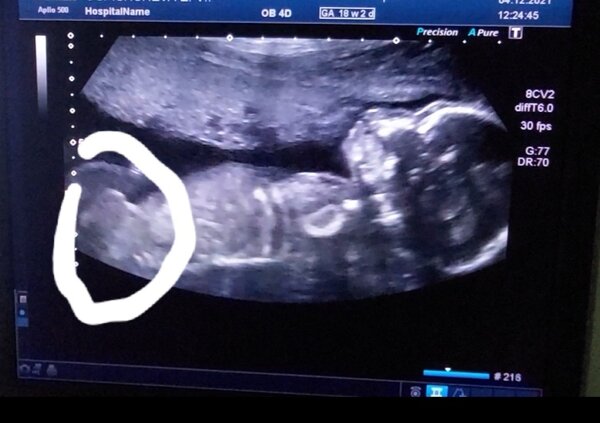

Особенности УЗИ при определении пола ребенка

Раздел: Идеи и советы